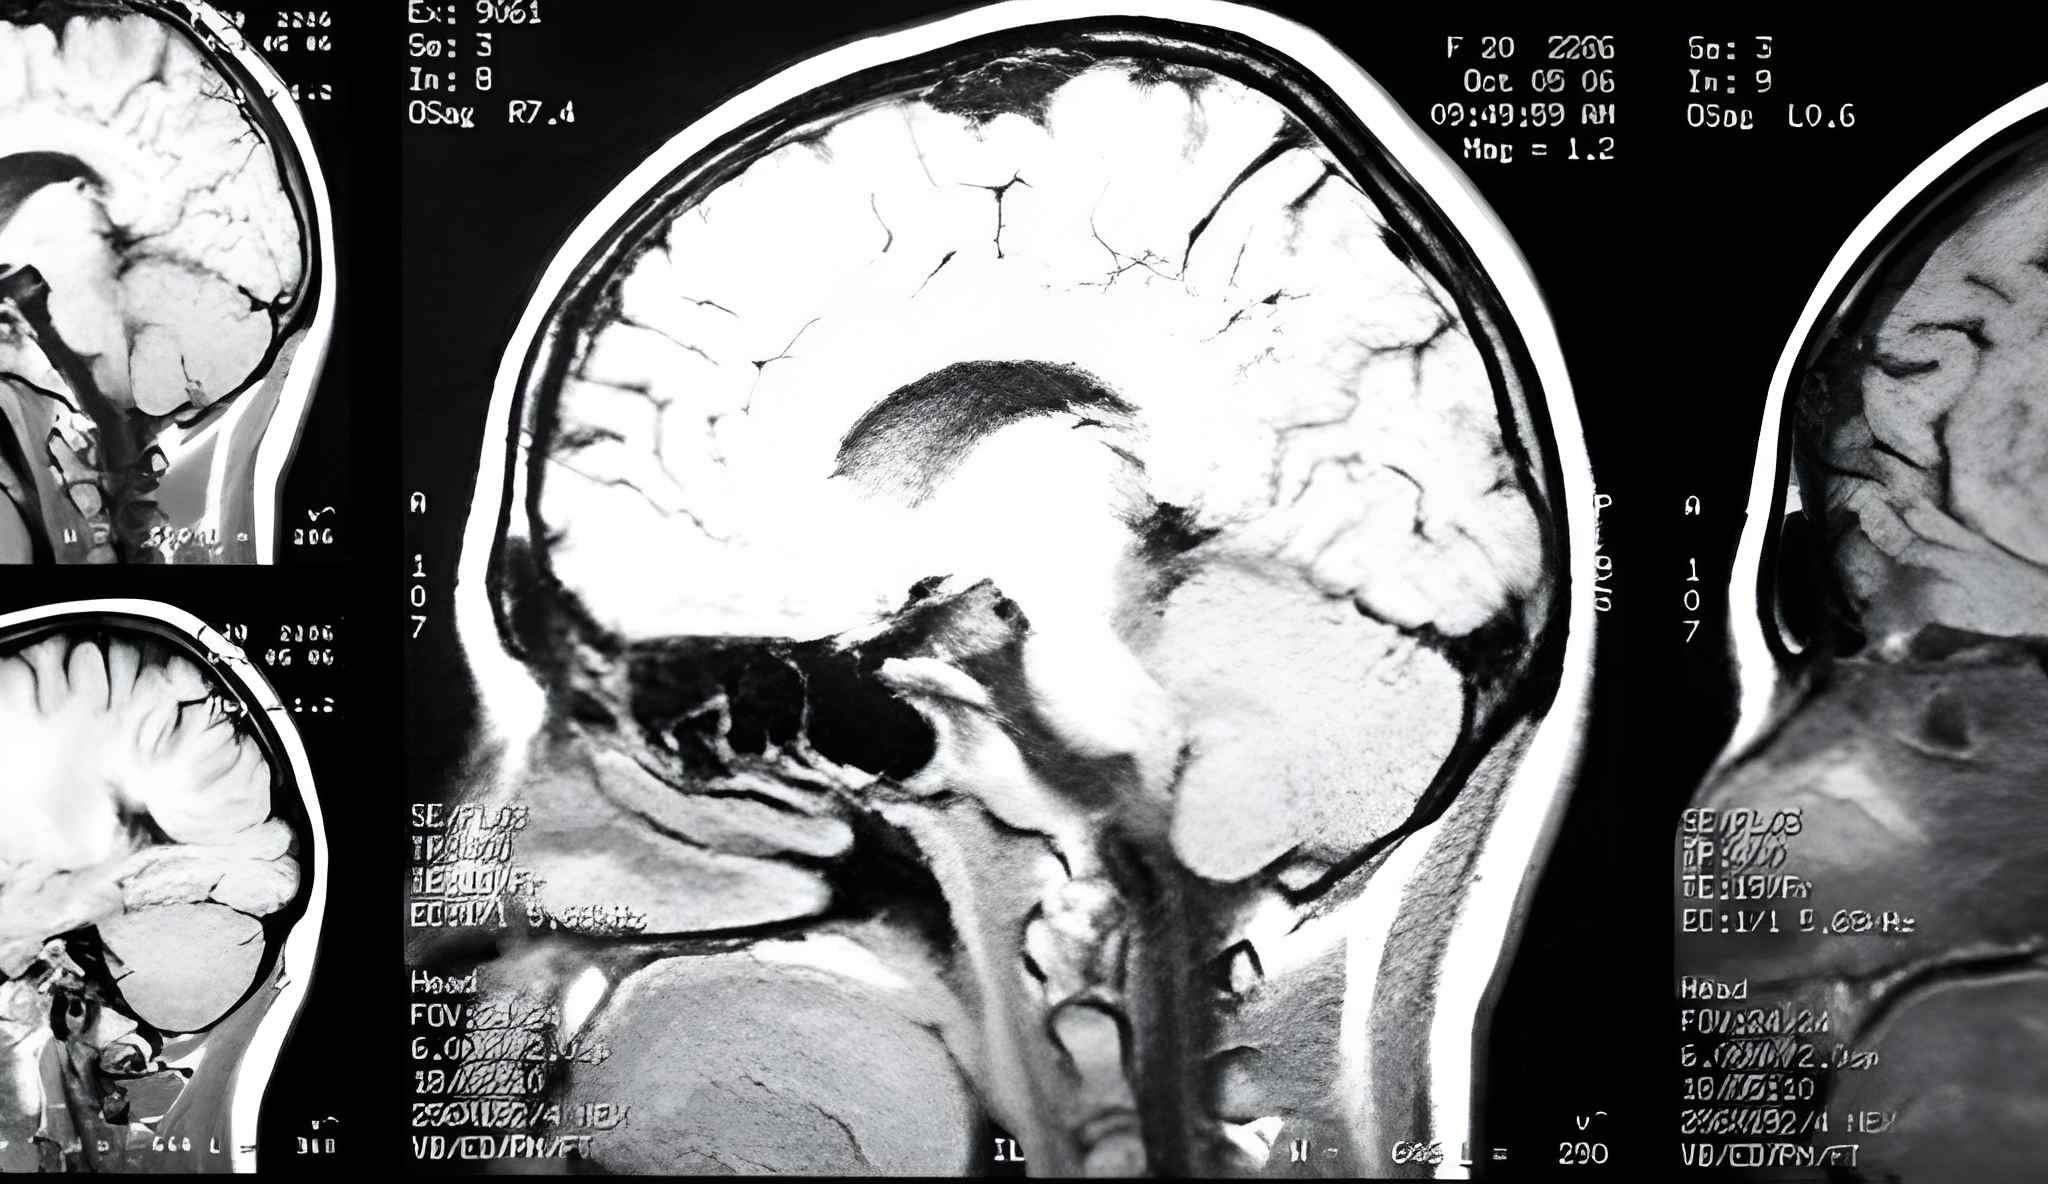

Chiari malformation is a rare neurological disorder where parts of the brain extend into the spinal canal, often causing headaches, balance issues, and motor difficulties. Growing awareness, improved diagnostic capabilities, and advancing treatment strategies are driving the growth of the Chiari Malformation Market, making it an area of increasing focus for healthcare providers, investors, and researchers.

Chiari malformations are categorized based on anatomical involvement and severity. Type I, the most prevalent form, is typically diagnosed in adolescents or adults, while Type II is more severe and often associated with spina bifida. Symptoms vary from mild dizziness to serious motor and sensory impairments. Accurate diagnosis usually relies on MRI scans, which provide detailed visualization of brain structures. Early identification is crucial to prevent complications like syringomyelia, a condition marked by fluid-filled cyst formation in the spinal cord.